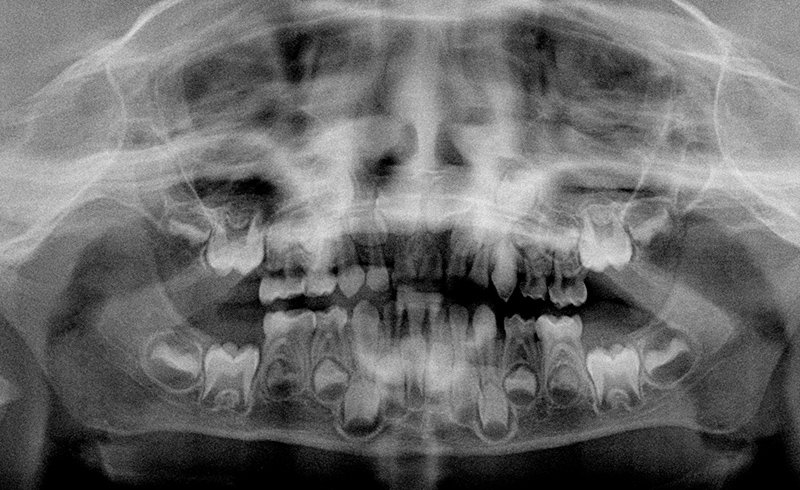

Gemeinsam mit den Eltern sorgen wir mit regelmäßigen Untersuchungen, Aufklärungs- und Vorsorgemaßnahmen für die Vermeidung von Karies und die Erhaltung des strahlenden Lächelns des Kindes vom ersten Zahn an.